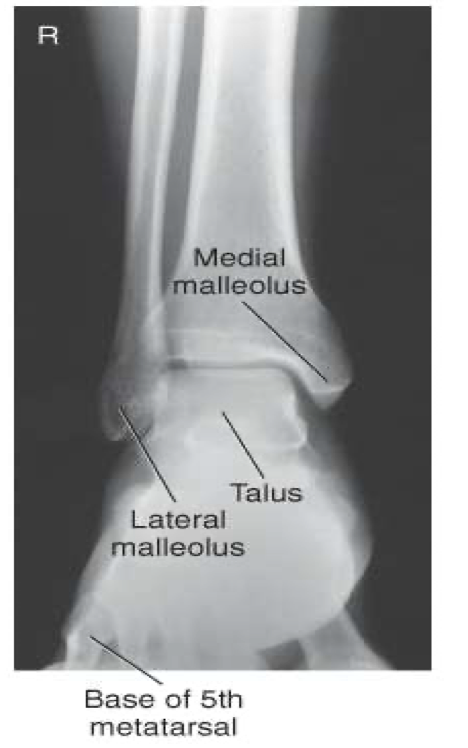

Lateral Ankle

CR

perpendicular to medial malleolus

Collimation

to include entire ankle joint, distal tib/fib and base of 5th metatarsal

especially the base of the 5th

Evaluation Criteria of lateral ankle

Entire talus and calcaneus visualized

Base of 5th metatarsal demonstrated

Lateral malleolus superimposed over posterior half of tibia

Talar domes superimposed & tibiotalar joint is open

Optimal exposure factors – visualize the distal fibula through the talus.

Should see anterior pretalar and posterior pericapsular fat pads

Note: Foot must be dorsiflexed 90° for anterior pretalar fat pad to properly demonstrated